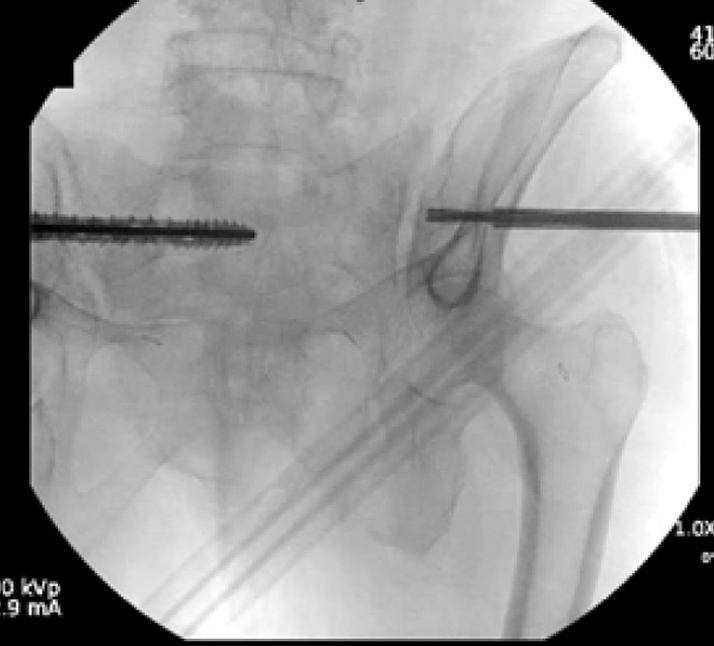

Surgical treatment:

• Bilateral sacral fracture fixation with iFuse TORQ®

Post-op:1,2

• Tolerated procedure well

• Immediate weight bearing as tolerated

• Ambulated 150 feet POD 1 and discharged home

• Pain improvement and healed fracture at 2 months

• No progression of kyphotic deformity